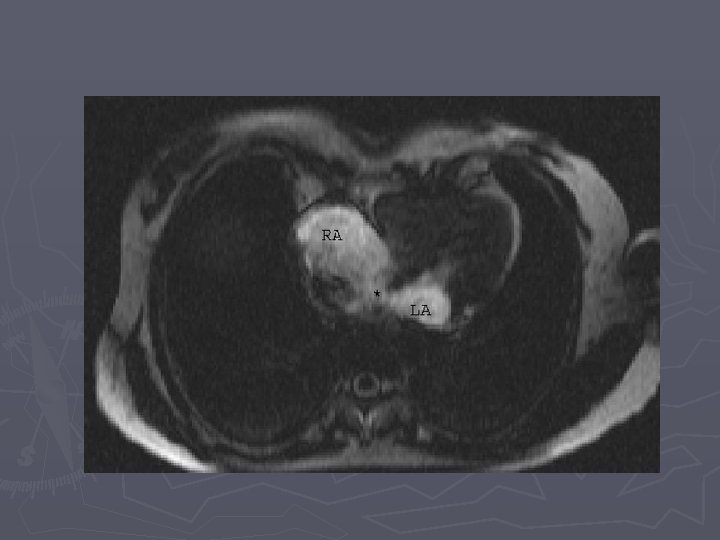

Imaging ASD ► Primary diagnosis made by echocardiography in infants and children ► MRI is emerging as accurate alternative for depiction of function, flow, and anatomy in older patients

Findings ► XR – small to moderate defects have normal radiographs ► XR - large defects have cardiomegaly with the main PA normal or enlarged, with shunt vascularity, later on PA and RV enlarge ► CTA – defect in atrial septum, enlargement of RA, RV and PA ► MR – can quantify shunt volume on volumetric cine MR or velocity encoded cine MR

ASDS, particularly the sinus venosus defects, are commonly associated with anomalous connection of the right pulmonary veins, pariticularly the upper lobe veinds to either the right atrium or SVC.